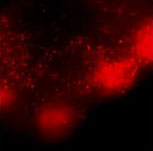

GLIOBLASTOMA SPREADS AMONG NEURAL TISSUE

The fluorescent glioblastoma grows rapidly inside the neural tissue. Semi-automatic quantification is applied to measure tumor area, in parallel, we monitor tumor dispersion and metastasis.

Fig. A: Topview of glioblastoma growth in the neural tissue 0-7 days post-inoculation. Fluorescence tumor imaging on the upper panel is quantified in a semi-automatized manner to obtain glioblastoma area in the bottom and right panels.